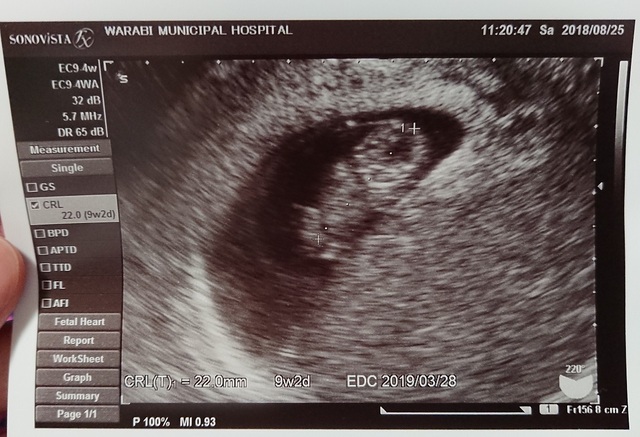

9週4日(9w4d・女の子)|llmitsui さん(36歳)

エコー写真撮影時のエピソード:つわりが現れ始めました。1日食欲がなく、吐きたくなる回数が増えました。電車に長時間乗ってしまう時に気分が悪くなるケースが多いです。

でもエコー写真を見てると、なんだか嬉しくて堪らないです。なぜか経腟超音波のほうが、お腹の上から撮影したものより、赤ちゃんっぽく見えてしまいます。